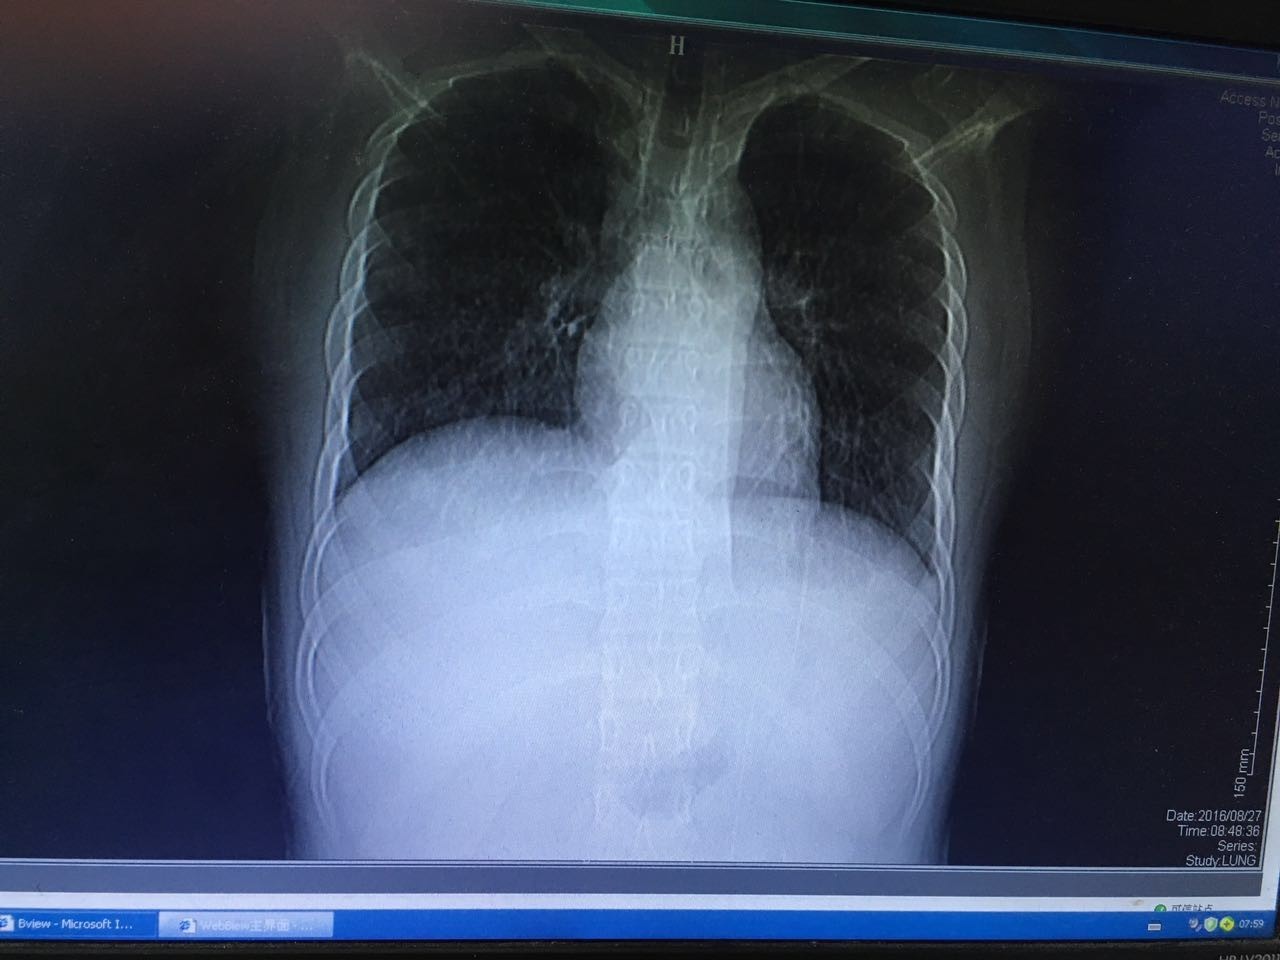

最后患者在治疗的过程中,联系了两位曾经和他在小河里摸鱼的朋友,居然都在高热。一个因为病情较重,已经转往省级医疗机构……治疗经过不详。还有一个因为肺部感染就住在我院呼吸科,我们后来接手了呼吸科的患者,也给 他完善了肠镜检查,获得了同样的结论。两人的肺部病灶及肠镜表现虽然轻重不同,但是基本上是类似的。(图片6-10)

图6

图7

图8

图9

图10